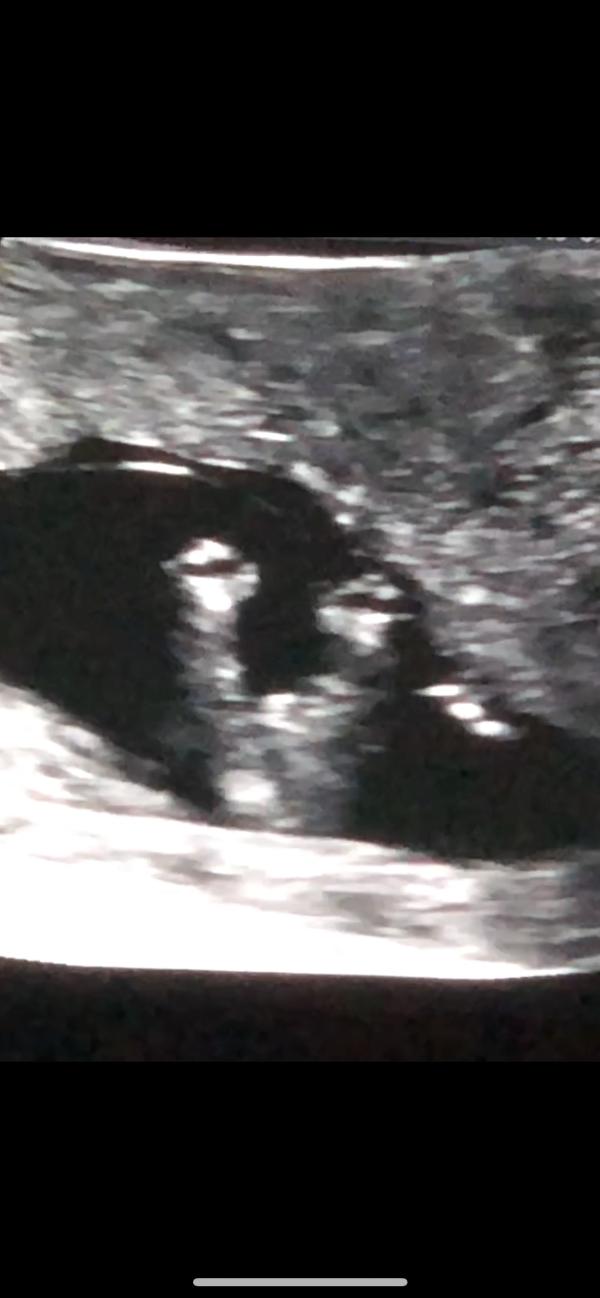

Okay so I went to the doc at 13 weeks 1 day and the lady was like I can’t tell the gender because it looks like it could be a swollen girl but not sure so she took two potty shots at different angles soo what do you ladies think? I need eyes lol I’m going today to find out the gender

@itty_bitty, yea that’s what I’m thinking but my boys have always been clear with the double stack lol

Those are swollen girl parts. My son was really obvious and my two girls looked like yours.

@denessev, so does the nub sticking up look like a girl? To me my boys have always been really obvious and this wasn’t obvious at all

@mommy_of_love, I really hope so I posted the images on my Facebook and every person said boy all because there’s a tiny bit there lol but everyone I don’t know says girl